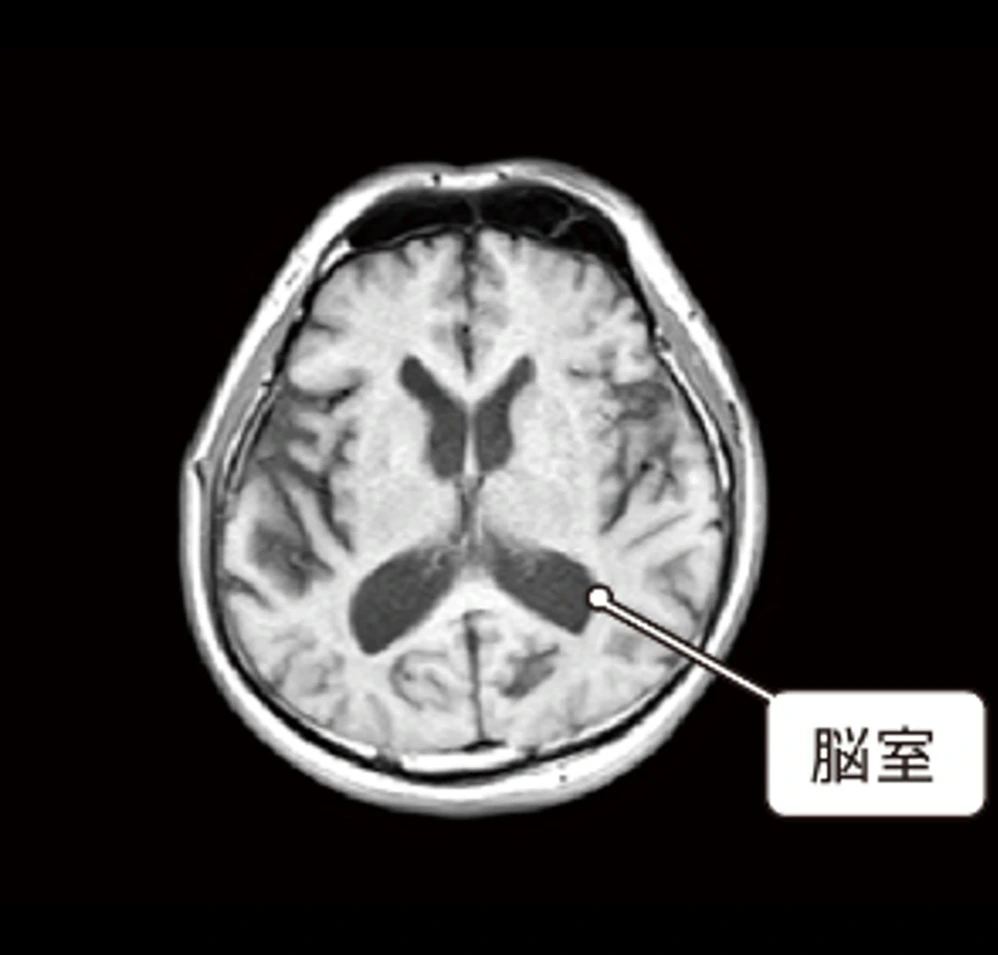

この2つの脳の画像は同じ50代の人のものです。上の脳画像は、中心にある暗いエリア(脳室という空洞部)が拡大しており、脳の萎縮が進んでいます。脳の萎縮は脳の機能低下や将来の認知症発症のリスク因子と知られています。60歳を過ぎても30代並みの若々しい脳を保っている方の例も多くあり、加齢による萎縮の進み方は人によって大きく異なります。

| T1強調画像 | 脳の損傷の部位を把握するのに有用 |